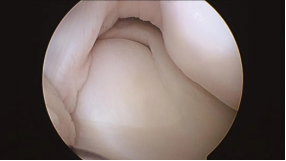

不完全型盘状半月板镜下观

图片来源:陈坚, 膝关节镜手术.人民卫生出版社 2014年4月

完全型盘状半月板镜下观

图片来源:陈坚,膝关节镜手术.人民卫生出版社 2014年4月